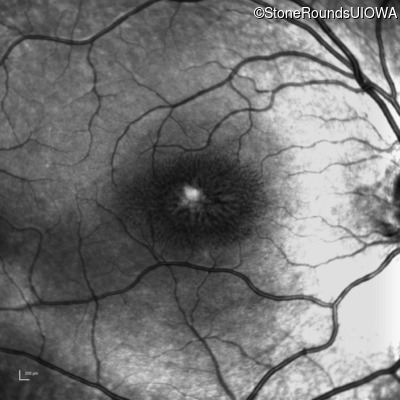

Infrared Fundus Photograph - Left - 20/40

Exemplar